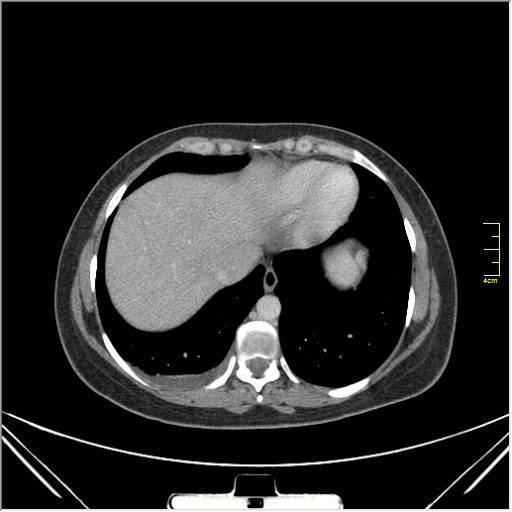

Женщина 32 года; месяц как кашляет. Повышения температутры тела не отмечала. Изначально выполнили рентгенографию. Что делать дальше?

Ок, мы определились с дифференциальным рядом при такой рентгенологической картине (Затемнение верхених сегментов правого лёгкого, S2). Какую рекоммендацию Вы бы дали такому пациенту? Что будем делать дальше?

Далее рекомендуем лабораторные исследования, КТ легких.

KT

Давайте определимся, для начала обозначим какие КТ признаки мы видим на представленных сканах. И главное это не перечисление вариантов диагнозов (если нет однозначного варианта); а определить что надо сделать следующим этапом для достижения окончательного диагноза.

Вполне адекватная тактика. КТ контроль через 3-4 недели после антибактериальной терапии, совершенно правильно.

В данном случае, пульмонолог решил пойти на бронхоскопию; был забор материала. Лабараторный анализ (ПЦР) выявил положительную реакцию на туберкулёз.